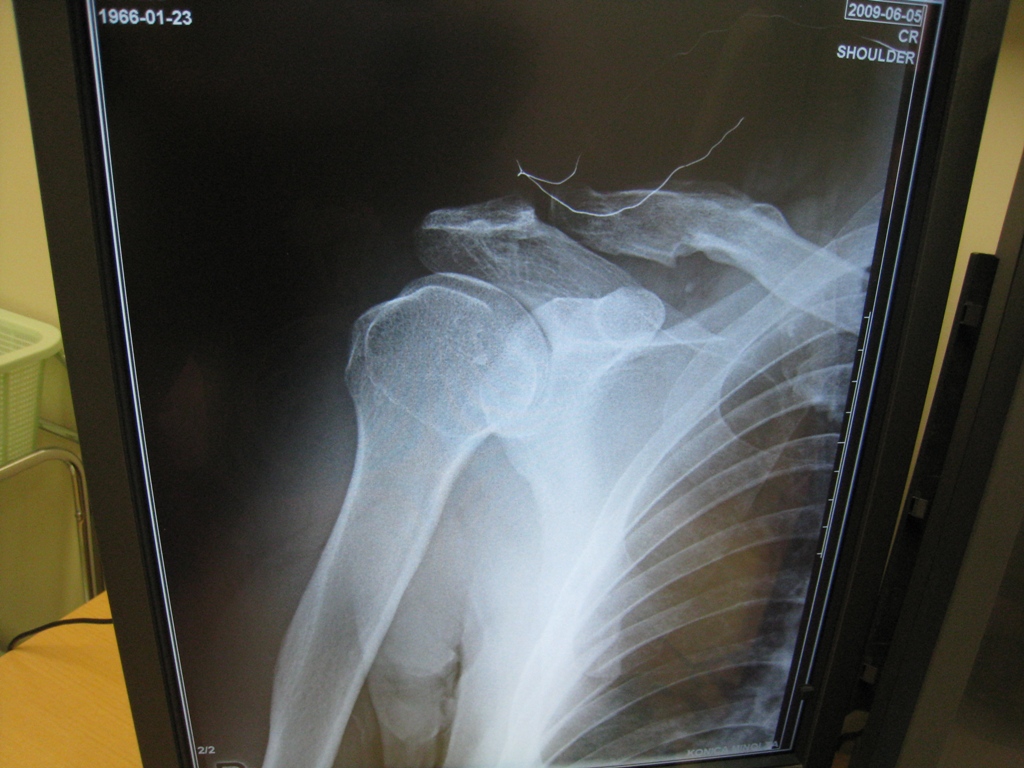

トレーニング中にヒョンなアクシデントから右肩を外傷性肩関節脱臼・靭帯損傷・・

お陰で短い時間で直ぐ検査をして、元通りにはめてもらったが、はめ込んでる時の更なる激痛は酷かった! それもはめ込むまで1時間以上もかかってやっとのことだったから始末が悪い。

損傷した肩は脱臼がクセや今後手術にならないように数週間は右腕固定・・・なんだって。

関節唇という軟骨を損傷しているため、しっかり固定しても再脱臼の危険性は高くなるらしく、関節唇ってのは二度と再生もしない。

まっ、今更再生しない人体部分を取り上げたらキリが無いし(笑)然程問題はないけど、 再発は勘弁!

数週間のギブス、、、 大事をとって今は固定しているけれども。

(写真左が脱臼しているレントゲン画像で、写真右が元に戻した後の画像)

左の写真は肩が下がり、残った部分はまるで、プロテクターのようになっていた。

骨を折る場所にもよるが、鎖骨折るよりは、はるか~に痛かった!